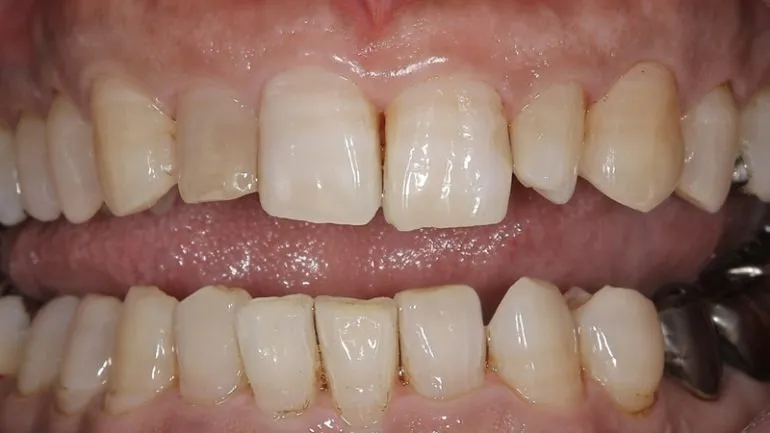

エアフローを使用したクリーニング

治療名

クリーニング

治療説明

治療回数

1回

副作用・リスク

呼吸器系の疾患や、薬剤によるアレルギー、妊娠・授乳期など、お身体の状態によってはエアフローが使用できない場合があります。

料金

保険適用

歯石がこびりついている場合も、保険適用でここまで綺麗になります。

最近歯医者さんに行けていない、または歯医者さんが怖いという方も、ぜひ一度ご相談ください。